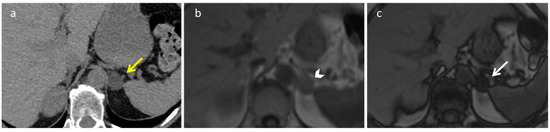

2.5. Schwannoma